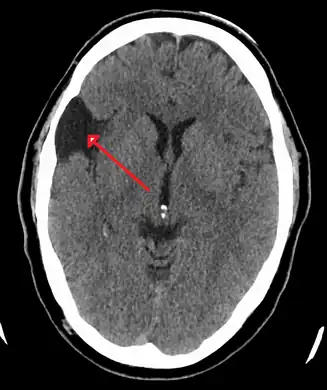

| A CT scan of an arachnoid cyst | |

CT scan of a colloid cyst

The diagnostic process typically begins with a medical history workup followed by a medical examination by a physician. Imaging tests, such as CT scans and MRIs, help provide a clearer picture. The physician typically looks for fluid (or other bodily substance) filled sacs to appear in the scans, as is shown in the CT scan of a colloid cyst. A primary health care provider will refer an individual to a neurologist or neurosurgeon for further examination. Other diagnostic methods include radiological examinations and macroscopic examinations. After a diagnosis has been made, immunohistochemistry may be used to differentiate between epithelial cysts and arachnoid cysts.[2] These examinations are useful to get a general idea of possible treatment options, but can be unsatisfactory to diagnose CNS cysts.[3][5] Professionals still do not fully understand how cysts form; however, analyzing the walls of different cyst types, using electron microscopes and light microscopes, has proven to be the best diagnostic tool. This has led to more accurate cyst classification and correct course of action for treatments that are cyst specific. In the past, before imaging scans or tests were available, medical professionals could only diagnose cysts via exploratory surgery.[2]